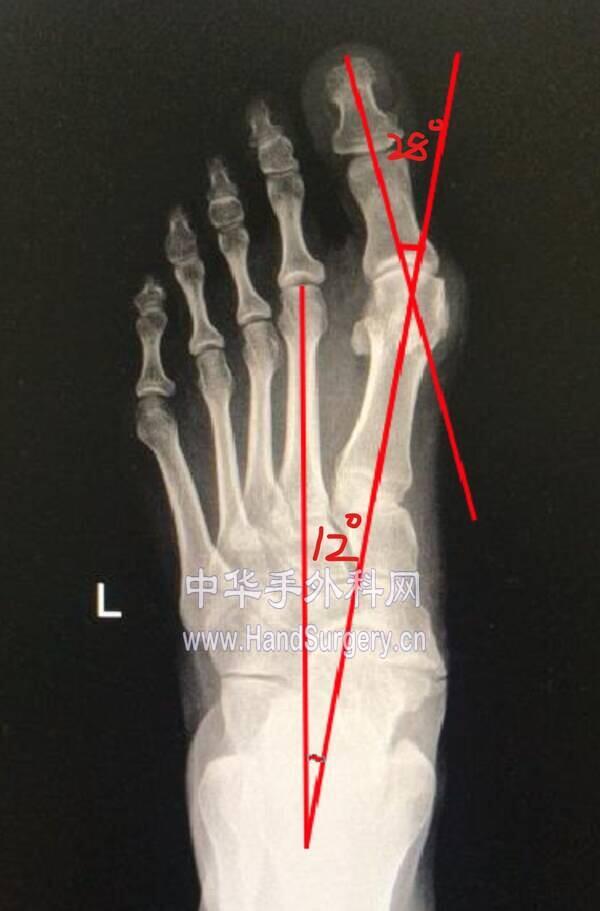

微信图片编辑_20191218175444.jpg 微信图片编辑_20191218175548.jpg

微信图片编辑_20191218175511.jpg 微信图片编辑_20191218175530.jpg

微信图片编辑_20191218175444.jpg 两侧均为中度

微信图片编辑_20191218175511.jpg